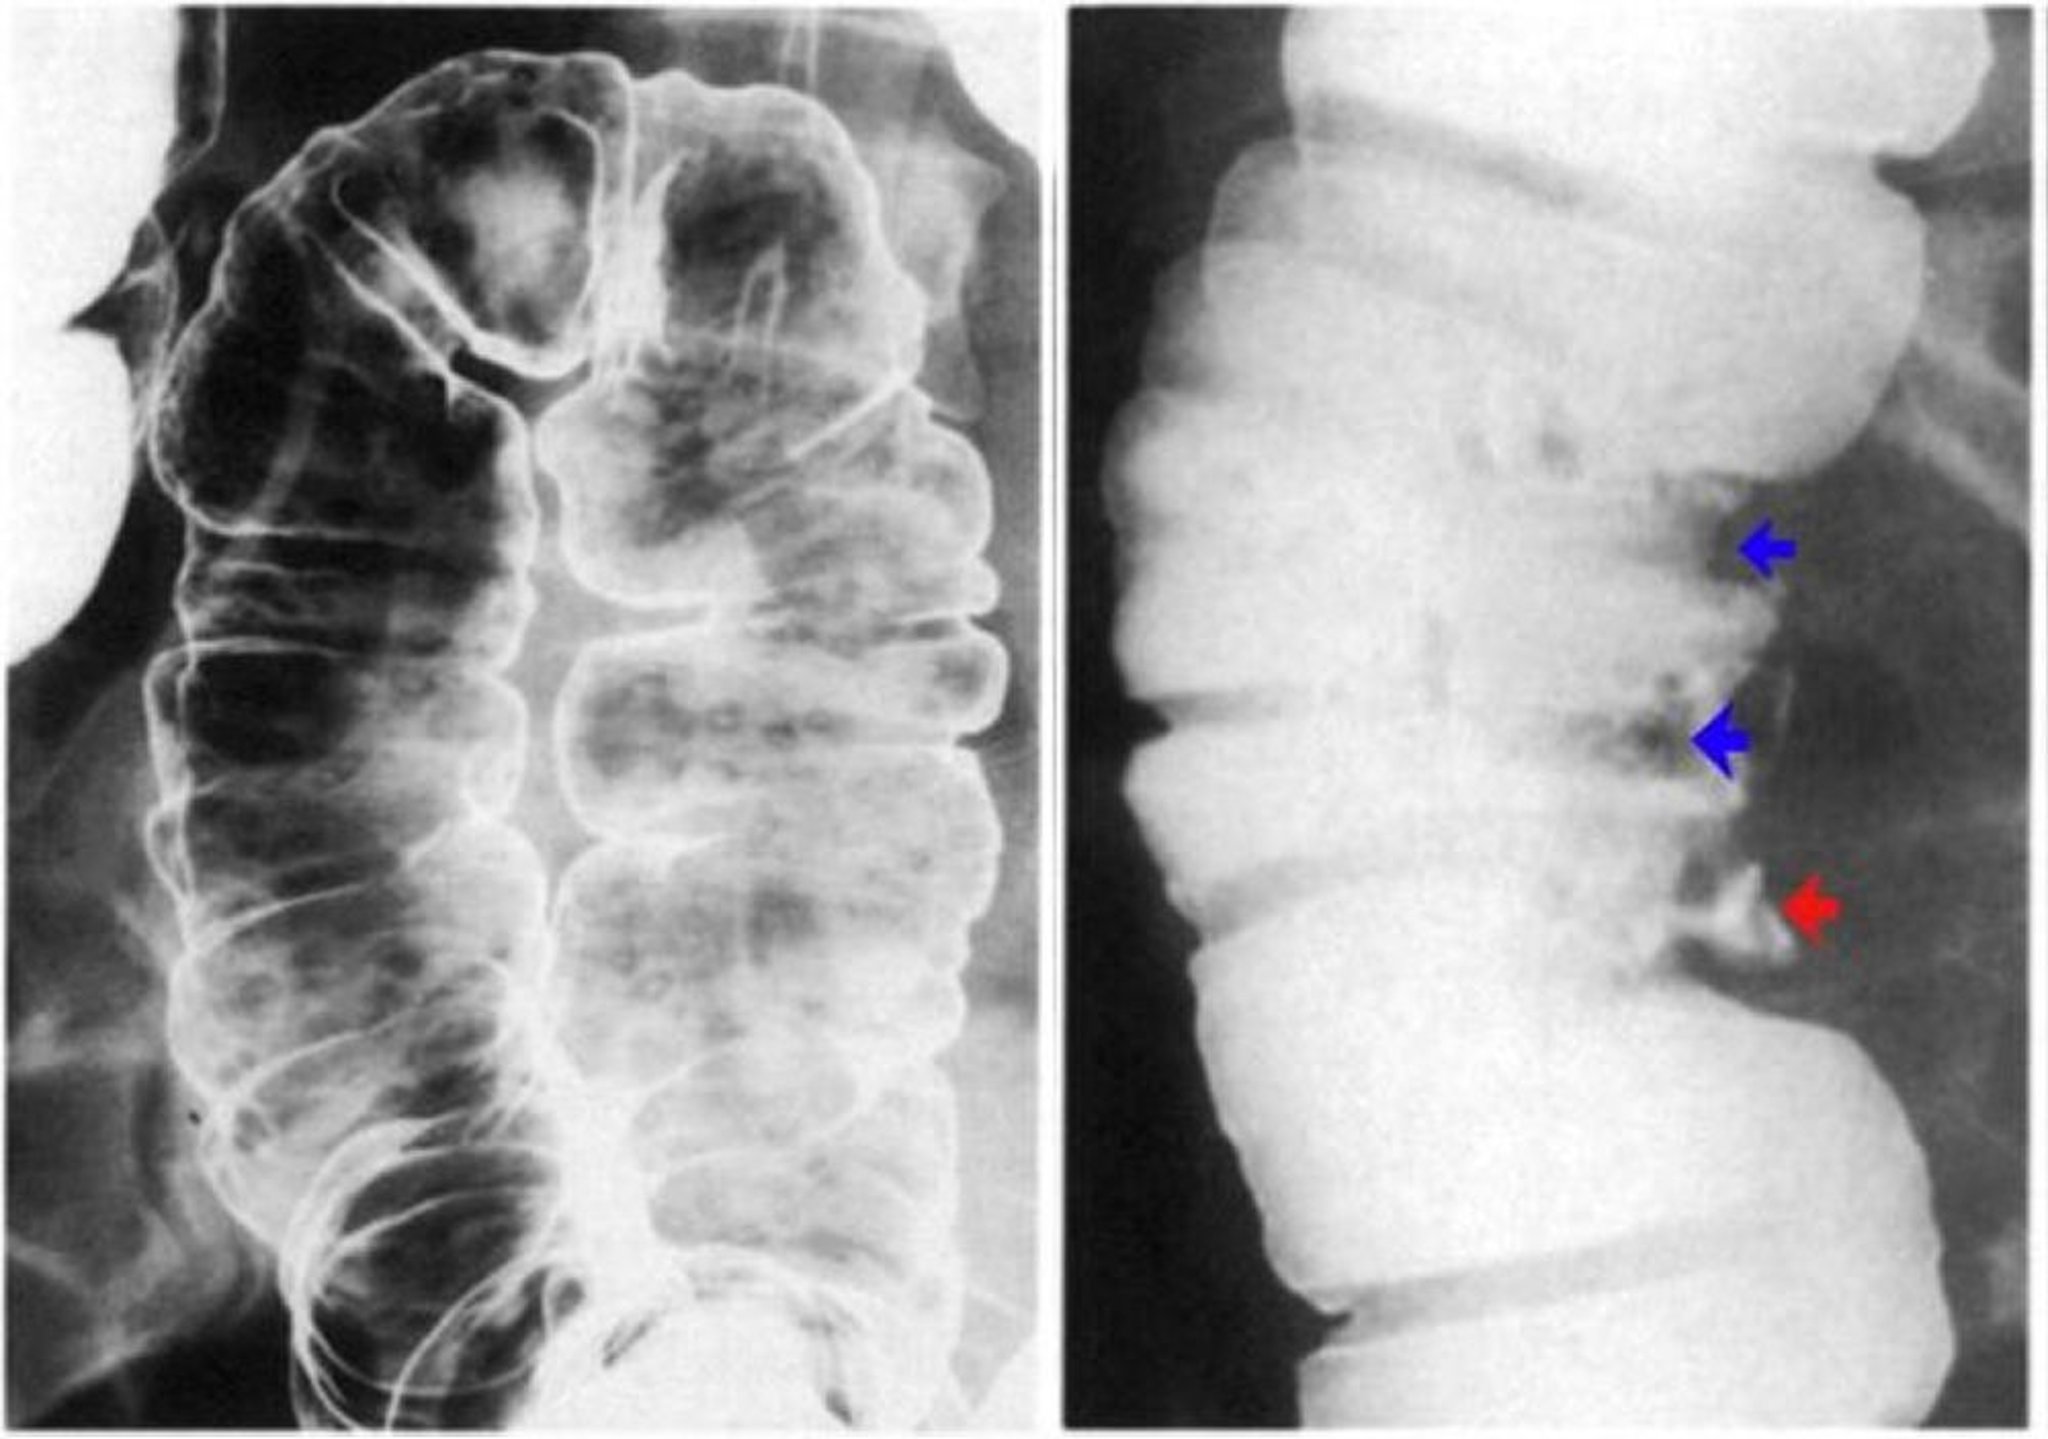

Thụt Barit có thể tiến hành như một thủ thuật cản quang đơn hoặc kép. Thụt Barit cản quang đơn được sử dụng khi có khả năng tắc nghẽn, viêm túi thừa, dò,và phình đại tràng. Thủ thuật với thuốc cản quang kép thích hợp để phát hiện các khối u.

Hình ảnh này cho thấy mô hình của không khí và bari trong một đại tràng bình thường.